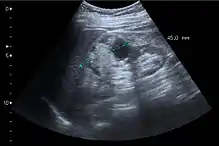

Figure 6. Complex cyst with thickened walls and membranes in the lower pole of an adult kidney. Measurements of kidney length and the complex cyst on the US image are illustrated by '+' and dashed lines.[1]